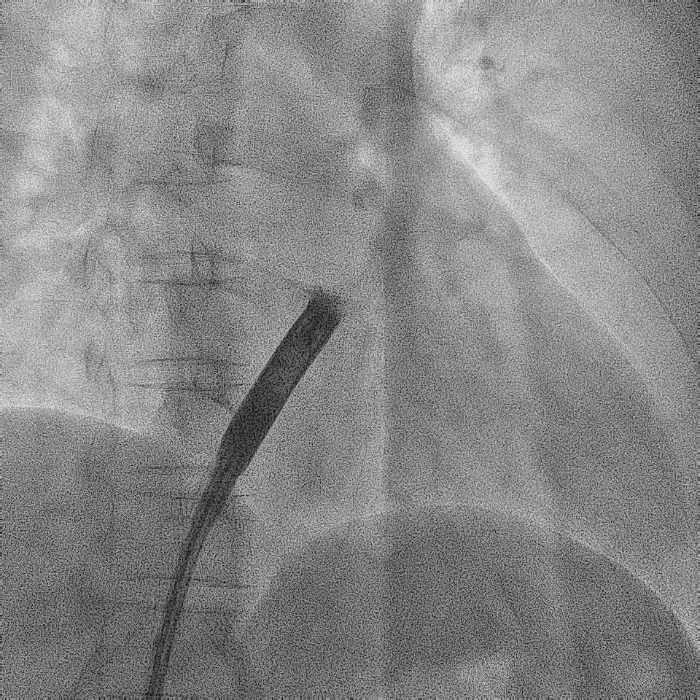

电极拔除

打开囊袋取出原起搏器后,使用锁定钢丝锁定分别锁定两根导线,备用激光鞘并未使用。直接徒手顺利拔除两根导线。

电极拔除过程